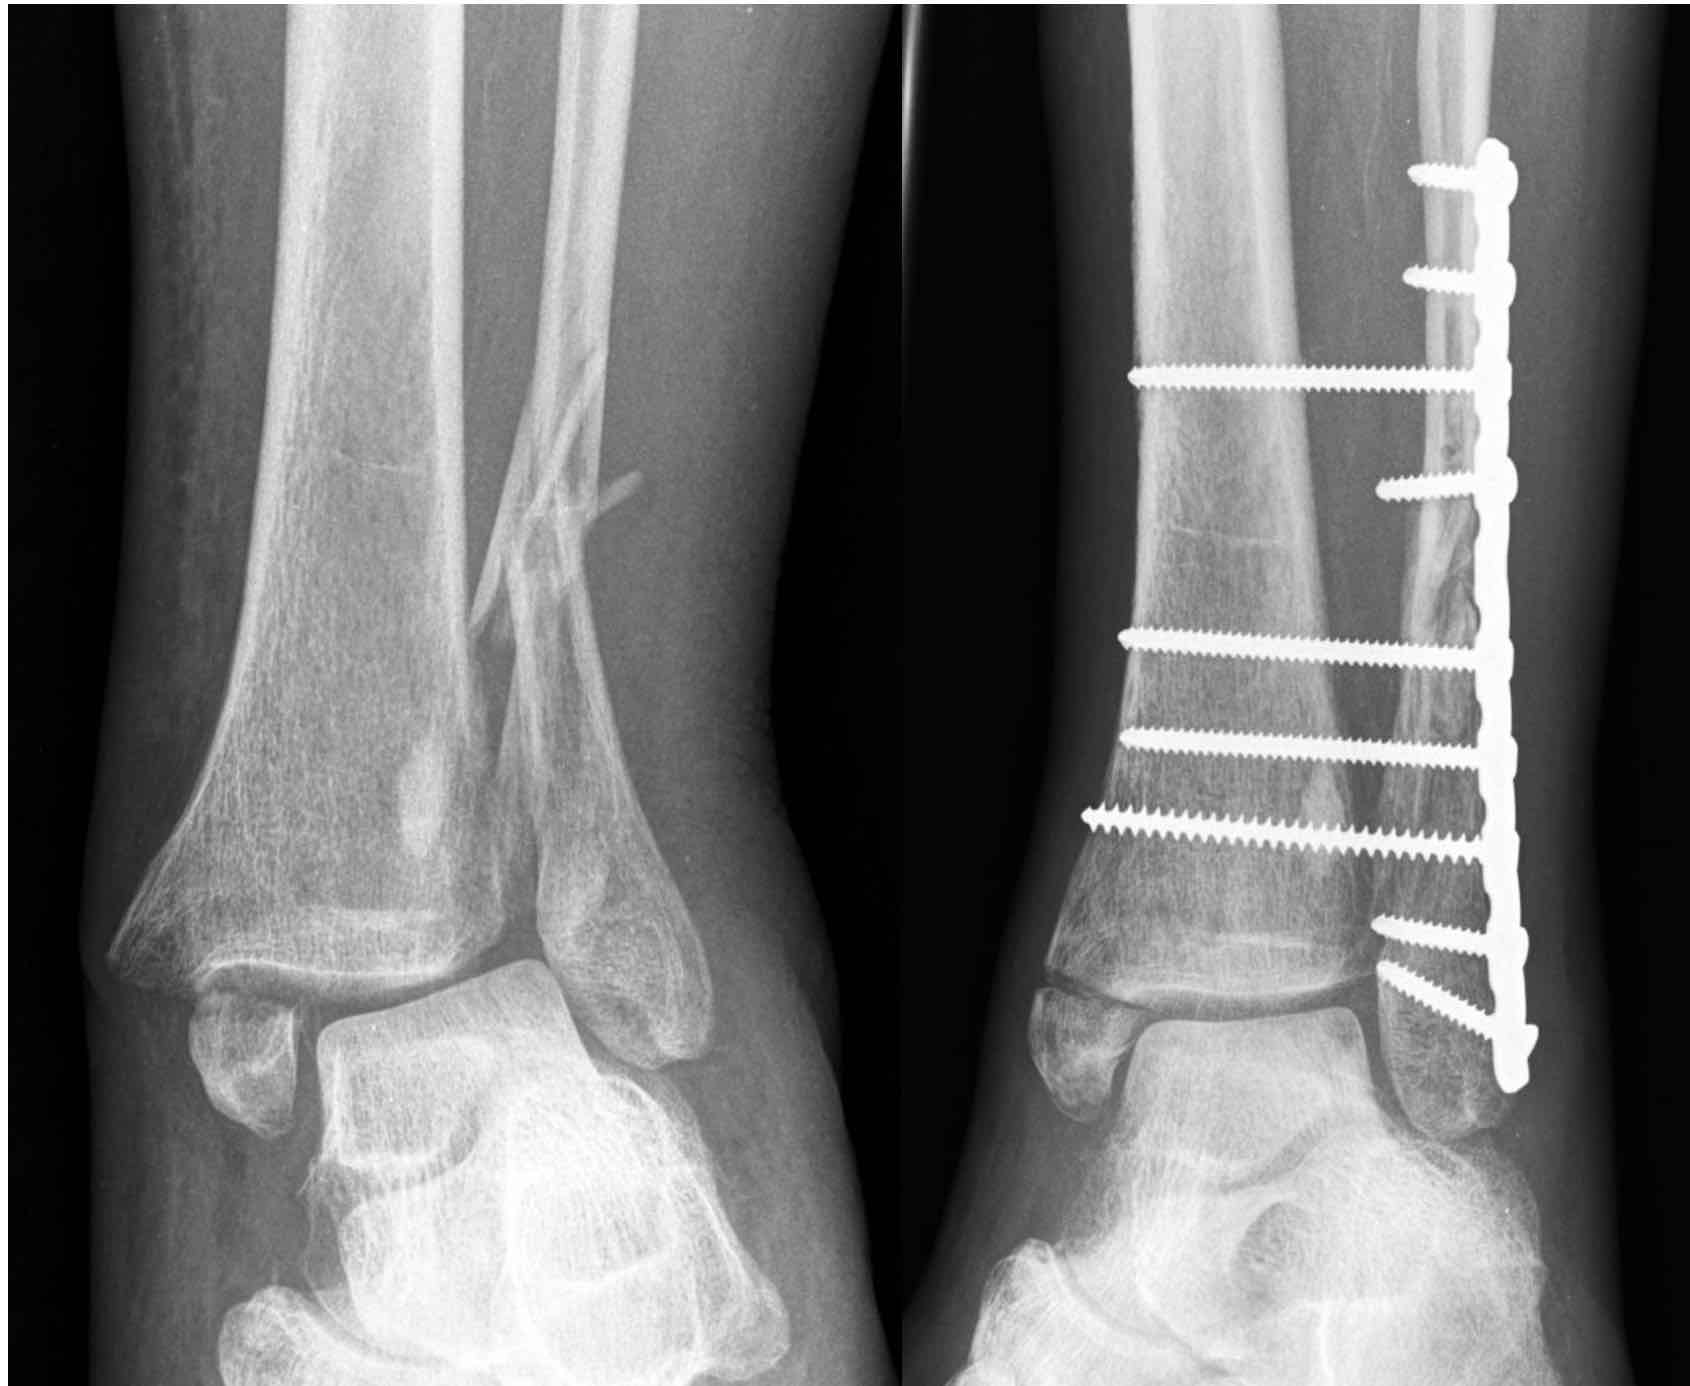

Augmented fixation or ‘ORIF plus’ is the mainstay of treatment for unstable diabetic ankle fractures.

Principles include:

- use of multiple tetracortical syndesmotic screws

- longer segment fixation

- use of locking plates

- consideration of transarticular pins to improve stability

Example of "Fibula pro-tibia" technique. Medial side left alone due to severe soft tissue compromise.